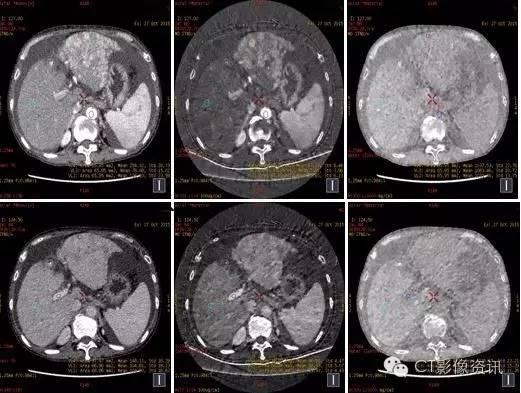

门静脉癌栓的显示

常规图像69keV

60keV

碘基图像

门静脉显示在60keV对比度更高,碘基图对含碘的结构显示非常敏感。